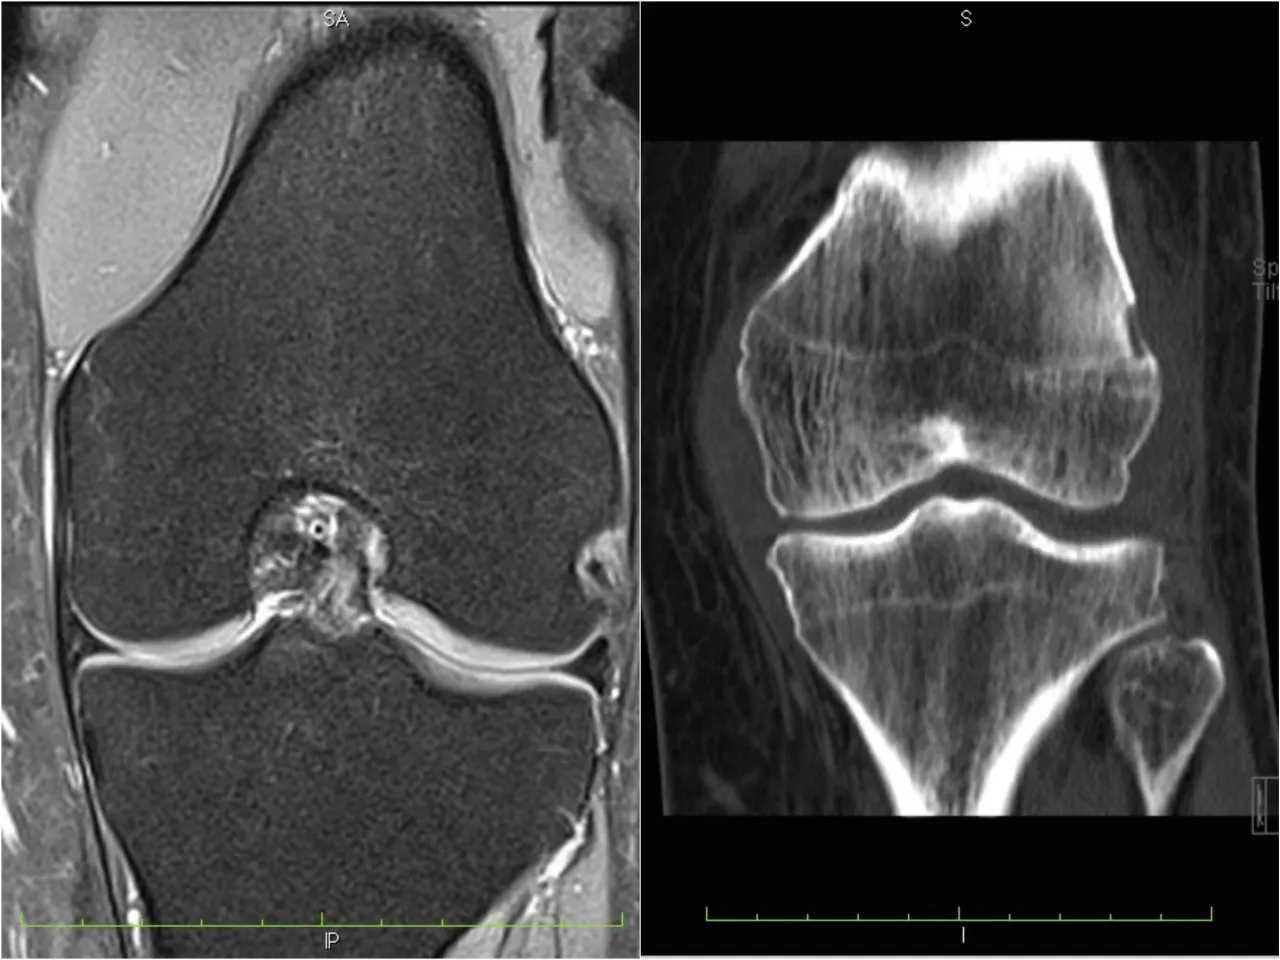

- Konieczność diagnostyki obrazowej: W wielu przypadkach do postawienia precyzyjnej diagnozy niezbędne są badania obrazowe. Ortopeda jest lekarzem uprawnionym do zlecenia i interpretacji takich badań jak RTG (rentgen), USG (ultrasonografia), MRI (rezonans magnetyczny) czy tomografia komputerowa. Są one kluczowe do oceny stanu kości, stawów, więzadeł i mięśni.

- Uraz kolana na nartach: Jeśli podczas jazdy na nartach doznałeś nagłego, silnego bólu w kolanie, poczułeś przeskoczenie, a kolano stało się niestabilne, powinieneś niezwłocznie udać się do ortopedy. Może to być podejrzenie zerwania więzadła krzyżowego lub łąkotki, które wymaga diagnostyki obrazowej i często interwencji chirurgicznej. Po postawieniu diagnozy i ewentualnym leczeniu operacyjnym, fizjoterapeuta będzie kluczowy w procesie rehabilitacji, pomagając odzyskać pełną sprawność i siłę mięśniową.